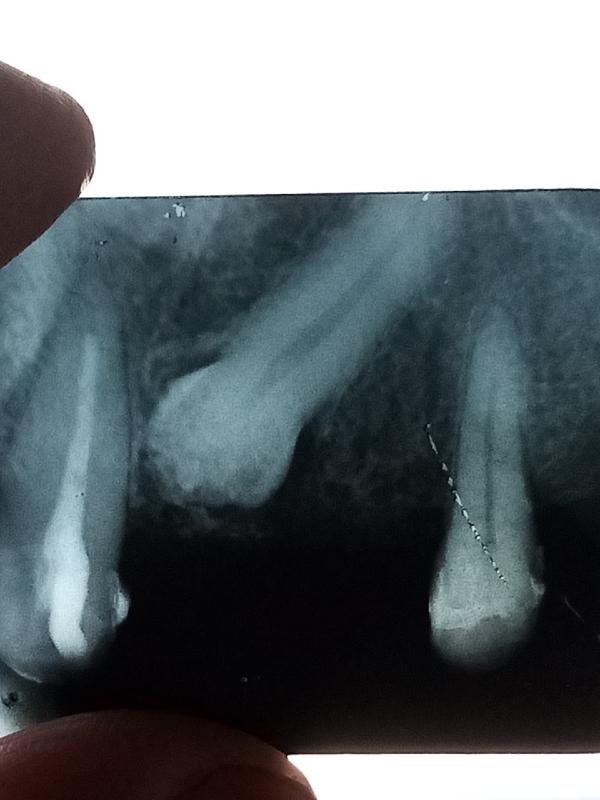

Обнаружили в 23 года зуб, который не прорезался и расположен под наклоном. Сейчас мне 52, уже 3 раза ставила мосты. Сейчас рекомендуют удалить этот зуб и поставить съемный протез, из одного города посылают в другой, в период коронавируса не делают плановые операции.

Может оставить и сделать коронки на одну сторону, на другую съемный протез? Может удалить зуб, в который упирается, и оставить тот, который в десне и делать съемный протез, но десна бывает, воспаляется и побаливает там, где упирается зуб внутри? Что делать, удалять зуб или нет?

Прикрепленые фото

Зависит от плана лечения. Этот зуб, можно даже поставить в зубной ряд, рекомендуем Вам проконсультироваться с ортодонтом очно.